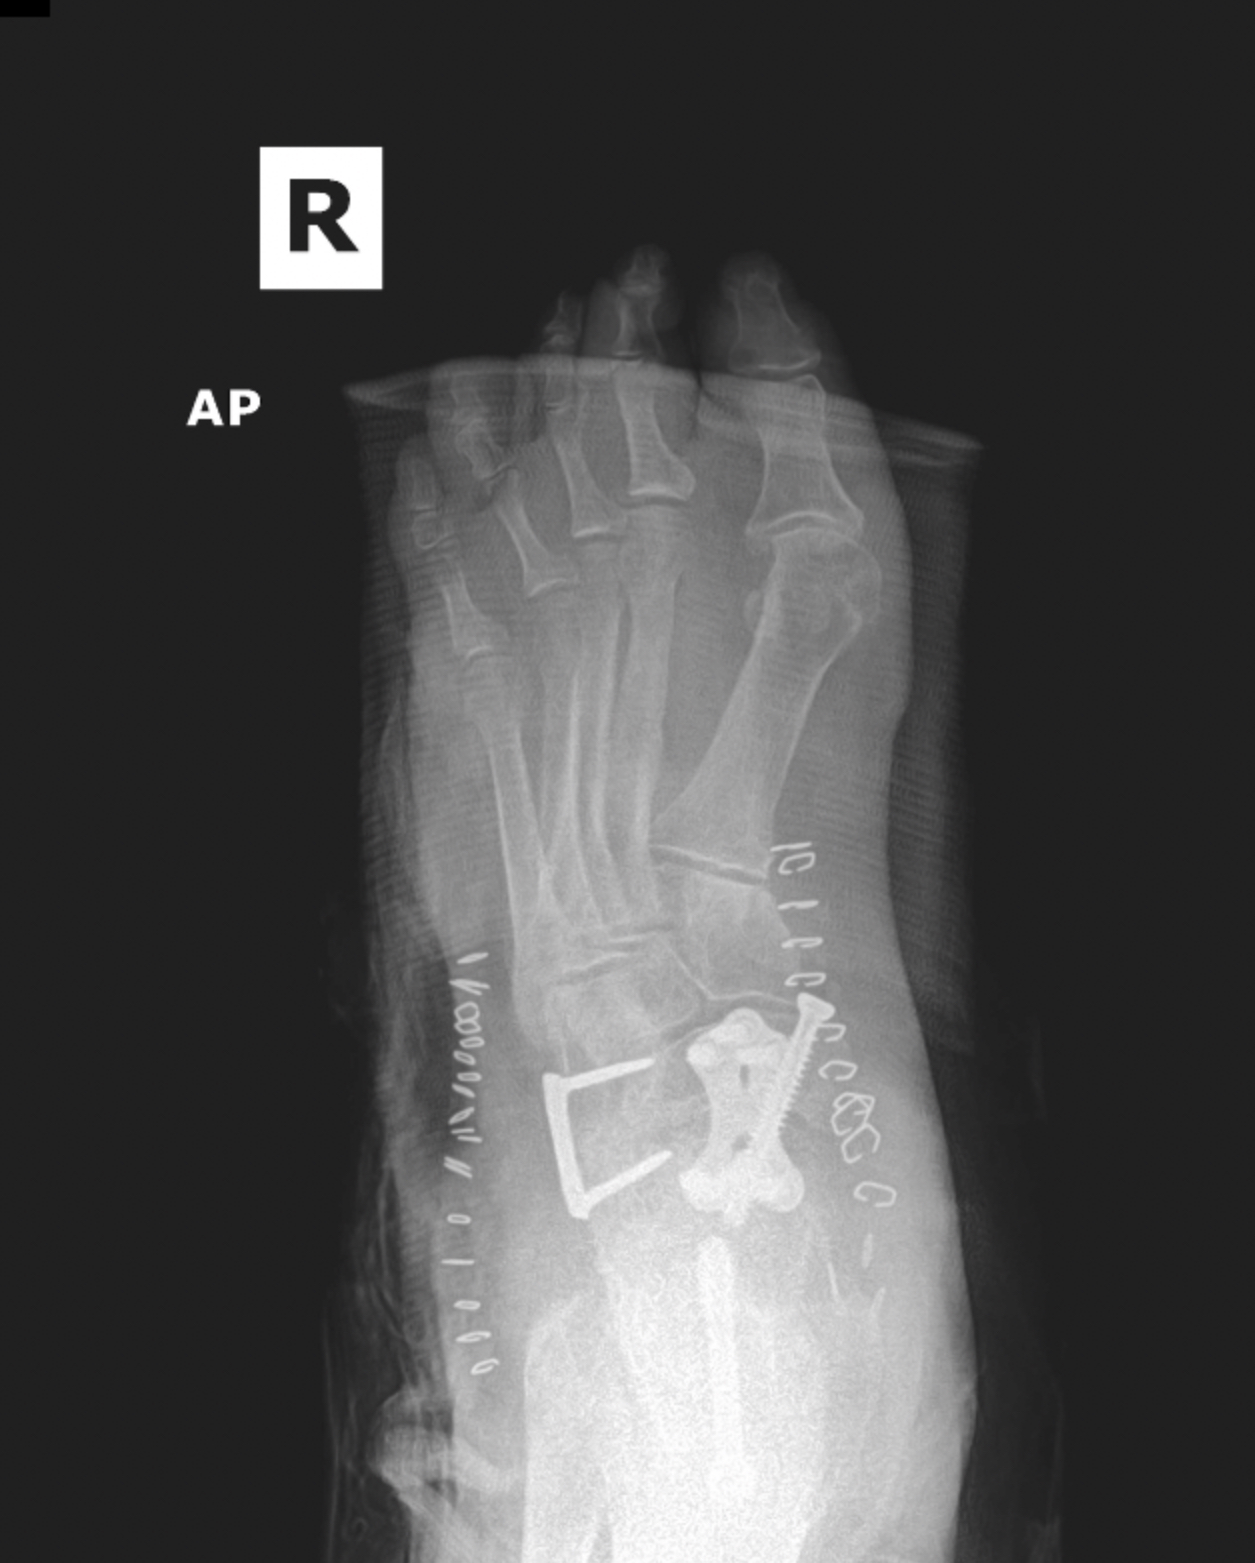

Ankle fracture repair

AF1